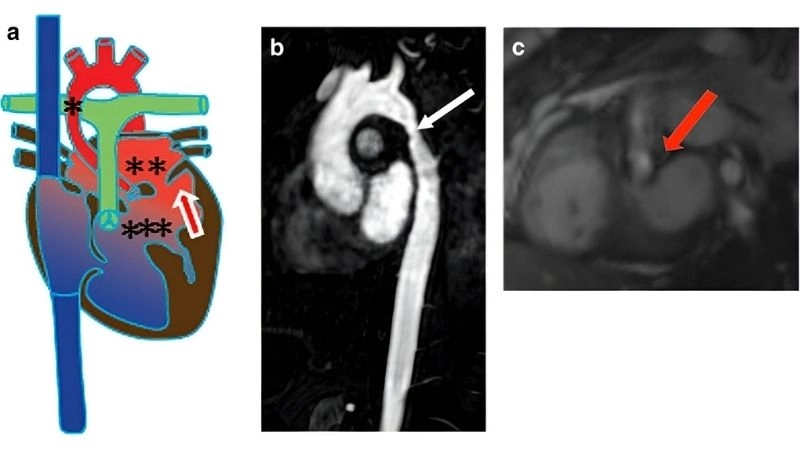

Shone's Complex is a rare congenital heart defect affecting the left side of the heart, often involving multiple obstructive lesions that impair normal blood flow.

Coarctation of the aorta dangerous narrowing of the artery